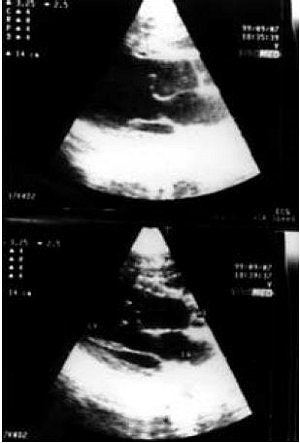

![]() |

| HCM is the most common cause of sudden cardiac death in young athletes and people younger than 30 years of age. In a normal heart, the heart walls are 11 mm or less in thickness (above and below). |